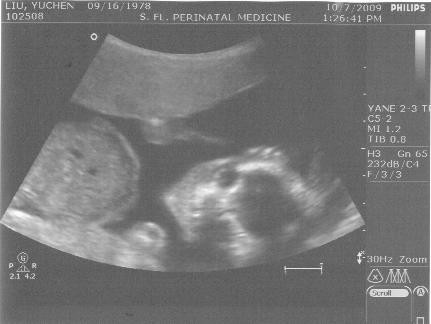

今天令人興奮的一點,就是要去照超音波啦!是招弟或是招財也會在今天揭曉答案,雖然說上次超音波時醫生已經有透露一些消息,但我就是硬要等今天週數多一點,會是確定的答案時再來相信

好啦~答案揭曉,是招弟

為娘的我下一胎會好好努力~今天超音波主要在觀察招弟的臟器發育情形不過很奇怪的是,上一次看人模人樣的招弟,很多部位像是四肢等,一看就知道,但是今天看到好多地方,以我對人體外觀的了解,竟然看不出來那是什麼,什麼胸腔啦,腹腔啦~不知道是招弟今天躺的位置比較怪異,還是因為是局部放大,我要是不問醫生,都以為那裡是頭哩!不過照到兩腿之間的時候,還是一眼就看出來了,是招弟沒錯

這到底是在照哪裡啊?

就是這個照片,證明是了招弟!醫生很樂天的打上

GIRL!!!殊不知為娘的我內心在淌血.

3. 給小猛媽,

我醫生是說兩腿中間很平坦, 沒有凸起物. 所以是女生.